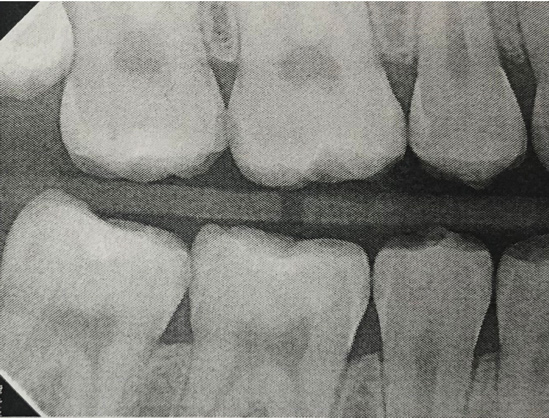

Interproximal insertion of SDF is demonstrated in different patients in Figure 3 through Figure 11. Various diameters and brands of soft dental picks may be used depending on the closeness of the proximal surfaces and ease of insertion; for example, some picks are designed for use in wider spaces between teeth. This protocol also offers versatility. Figure 3, for example, shows the simultaneous use of three thin soft dental picks to saturate proximal surfaces with SDF in a teenaged patient; the treated regions were subsequently covered with fluoride varnish (Figure 4). This patient was initially treated in April 2019 (Figure 5), with an identical re-application 3 months later. As shown in Figure 6, the December 2019 bitewing film revealed good results with the possible exception of the contact regions of the maxillary first and second molars. New SDF application was completed in the December appointment.

Fig 5. Three thin soft dental picks were used simultaneously for SDF proximal surface saturations in a teenaged patient (Fig 3). After 60 seconds, the treated regions were covered with 5% fluoride varnish (Fig 4). A comparison can be seen of pre-SDF-treatment bitewing films (Fig 5) and 8-month post-SDF bitewing films (Fig 6) for the patient shown in Fig 3 and Fig 4. Radiolucencies were similar or improved, except for contact of maxillary first and second molars.

Figure 5

Fig 6. Three thin soft dental picks were used simultaneously for SDF proximal surface saturations in a teenaged patient (Fig 3). After 60 seconds, the treated regions were covered with 5% fluoride varnish (Fig 4). A comparison can be seen of pre-SDF-treatment bitewing films (Fig 5) and 8-month post-SDF bitewing films (Fig 6) for the patient shown in Fig 3 and Fig 4. Radiolucencies were similar or improved, except for contact of maxillary first and second molars.

Figure 6